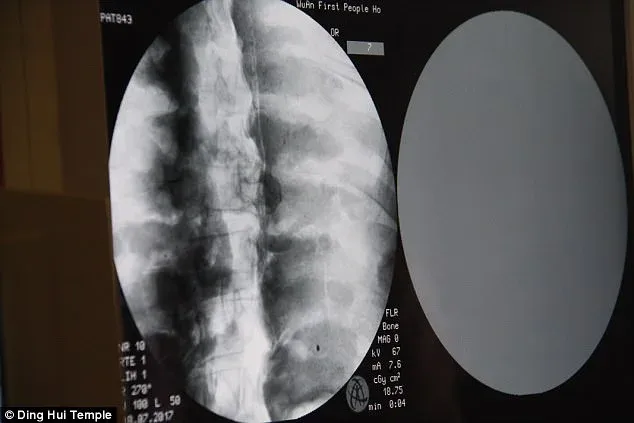

ภาพจาก CT Scan เผยให้เห็นรายละเอียดชัดเจน

ตั้งแต่โครงกระดูก ฟัน ซี่โครง ไปจนถึงกระดูกสันหลัง

ทุกส่วนยังคงอยู่ครบอย่างน่าทึ่ง แม้เวลาจะผ่านไปกว่าพันปี